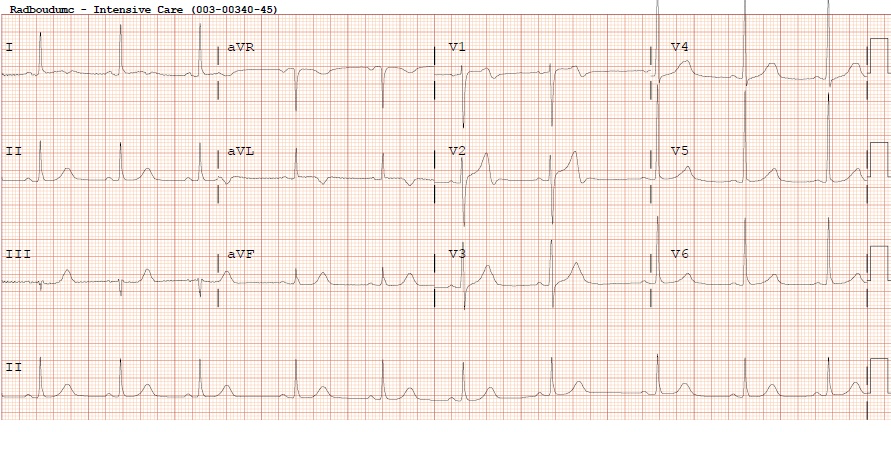

Figuur 3 – Elektrocardiogram op de intensive care

Sinusritme, normale hartas, normale geleidingstijden, negatieve T-toppen I, aVL. Bifasische T-toppen in afleidingen V1 en V2. Dit ECG past bij een evoluerend anterolateraal infarct.